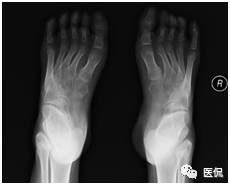

主诉 :主诉:双足内收、内翻畸形,呈马蹄状,且随年龄增长逐渐加重。

现病史:双足明显内翻、内收畸形,跟腱及跖筋膜挛缩、紧张,双足距骨、骰骨均脱位,骰骨外凸形成滑囊,双足跟内翻,尖小,双足背外侧着地负重,内踝深陷,背伸活动功能障碍,不能独立行走,双小腿肌肉萎缩。

足部非负重正位片:足前部明显内收,跖骨远端及趾骨平铺,跖骨近端聚拢、外移;第1跖骨萎缩,第5跖骨肥大,密度增高;距骨扁而宽,距骨中轴线明显远离第1跖骨,跟骨内翻呈马蹄状,跟骨中轴线明显远离第5跖骨,跟距关节半脱位;跗骨形态失常,舟骨外侧发育较小,相应部分与距骨形成关节中创网,但距舟关节半脱位,跗骨关节间隙变窄;胫骨远端骨化中心外侧部分较内侧部分明显扁小。

因常规正位片踝部跟骨、距骨、跗骨及胫腓骨重叠较多,诸骨形态失常、变化较大,且测量误差增大,很小的位置改变即可改变足骨的关系,所以只要可能,正位、侧位片都应行负重位检查,但负重正位片受设备及投照的限制不易达到,因此角度的测量主要在负重侧位片上进行才更有价值。